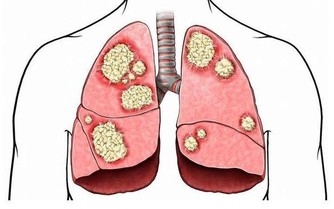

黑色糞便是消化系統腫瘤常見的特徵,在局部腫瘤不斷發展之後體積增大,血液供應豐富的腫瘤破裂出血,血液流失之後和糞便混合,排泄出體外時顏色已經改變,可以發現原本黃褐色的糞便變成了黑色,還可能有腥臭氣味。

這種情況代表出血量較多。需要通過檢查判斷是胃癌還是腸癌引起,通過正確治療來改善病情。